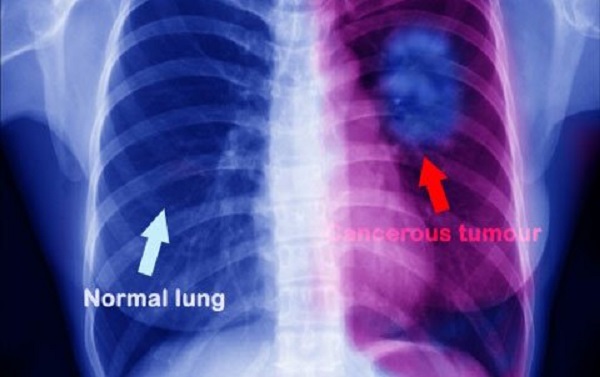

4 Lung Cancer Most Common Cause Of Cancer In The United States

Among the types of cancer, lung cancer was at the top with 184,970 cases and 132,960 deaths. Colorectal cancer is at second position with 76,910 cases and 28,290 deaths. As per the research data, 1,596,486 new cases of cancer and 591,686 deaths were seen in the United States in 2014 (latest year with available incidence data).